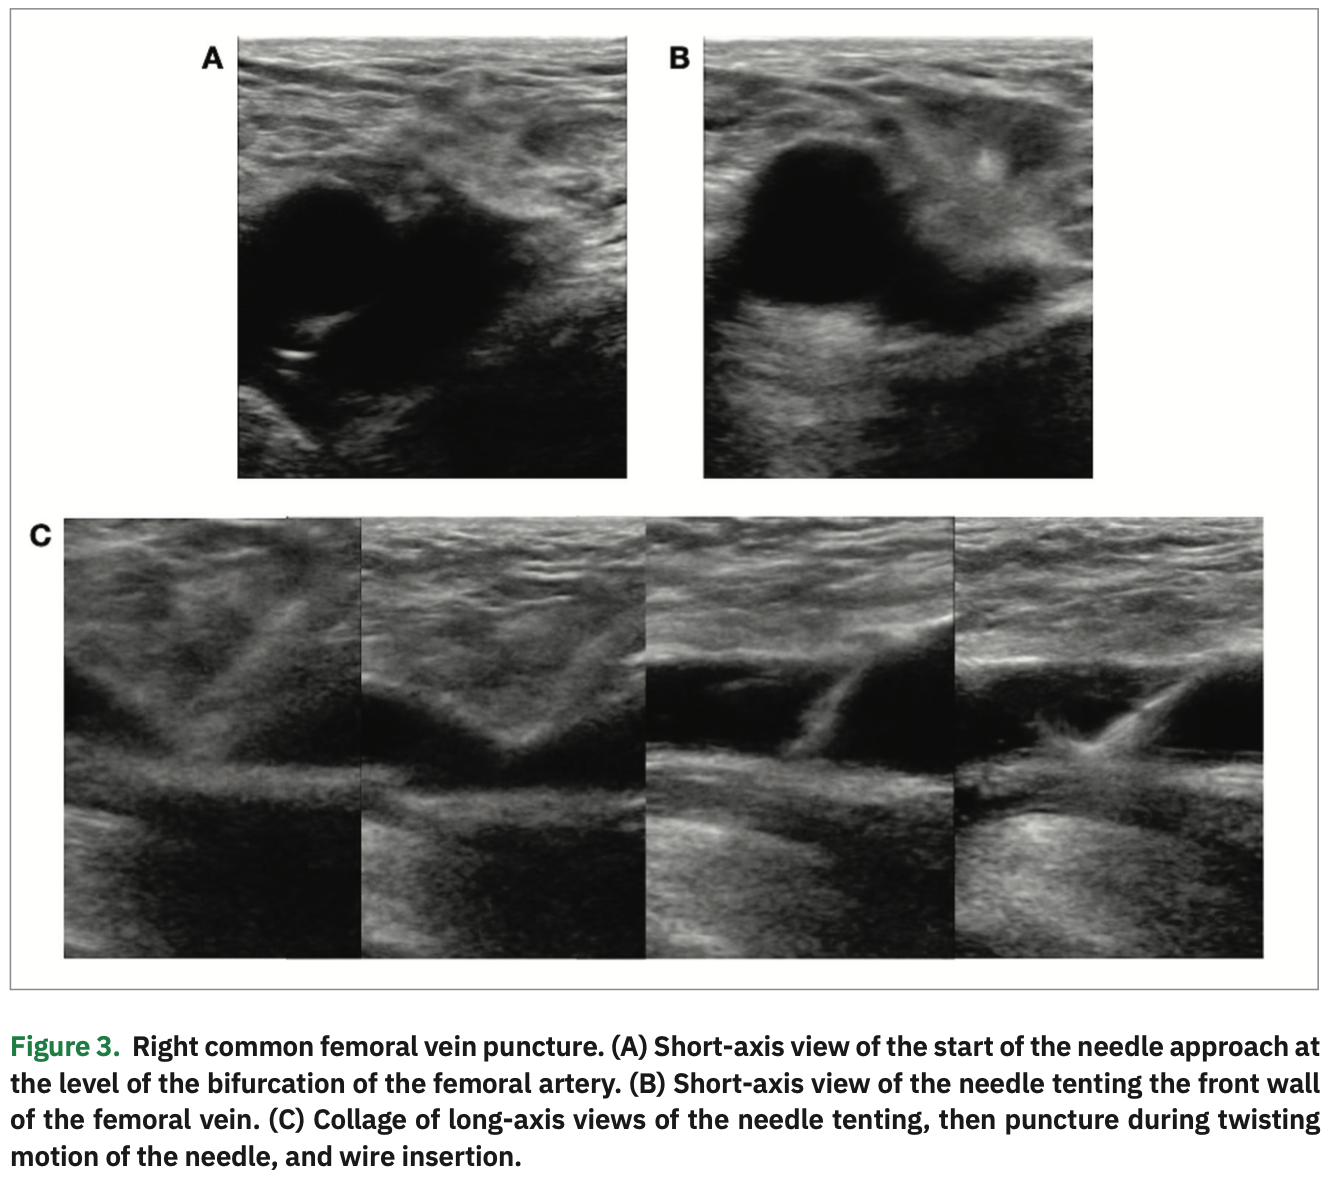

From www.hmpgloballearningnetwork.com

Integrating LongAxis and ShortAxis Views with a Twist for Ultrasound Short Axis Vs Long Axis  To the best of our knowledge, this is the first systematic review and meta. The short axis (sa) approach and the long axis (la) approach. Short Axis Vs Long Axis.

Integrating LongAxis and ShortAxis Views With a Twist for Ultrasound Short Axis Vs Long Axis  The short axis (sa) approach and the long axis (la) approach. To the best of our knowledge, this is the first systematic review and meta. Short Axis Vs Long Axis.